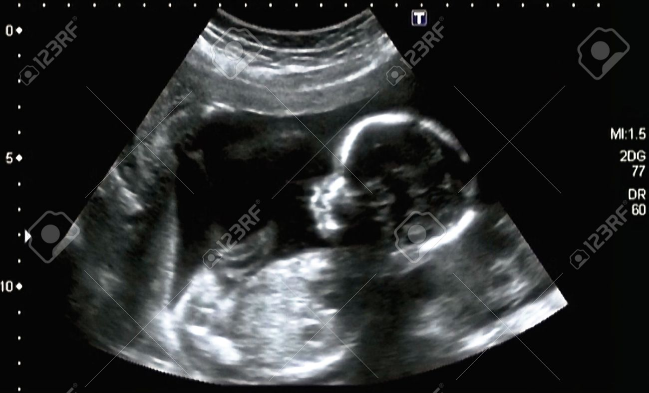

[b][size=100][size=150]Con [color=#ff0000]l'ecografia [/color]si ottiene l'immagine di un feto nel ventre della madre, misurando i [color=#ff0000]tempi di riflessione degli ultrasuoni che vengono inviati sulle sue diverse pareti[/color].[/size][/size][/b]

Con l'ecografia si ottiene l'immagine di un feto nel ventre della madre, misurando i tempi di riflessione degli ultrasuoni che vengono inviati sulle sue diverse pareti.